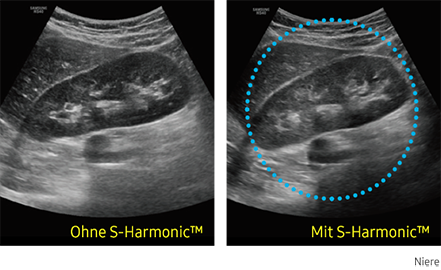

S-Harmonic

Diese neue Harmonic-Imaging-Technologie bietet Ihnen homogene Ultraschallbilder vom Nah- bis zum Fernfeld bei gleichzeitiger Rauschunterdrückung. Kombiniert mit den S-Vue™-Sonden und der S-Vision™ Imaging Engine erzeugt die HS40 Bilder in hoher Qualität.

Ultraschallbild Niere links ohne S-Harmonic und rechts mit S-Harmonic. Ultraschallbild Niere links ohne S-Harmonic und rechts mit S-Harmonic. Ultraschallbild Niere links ohne S-Harmonic und rechts mit S-Harmonic. Ultraschallbild Niere links ohne S-Harmonic und rechts mit S-Harmonic.